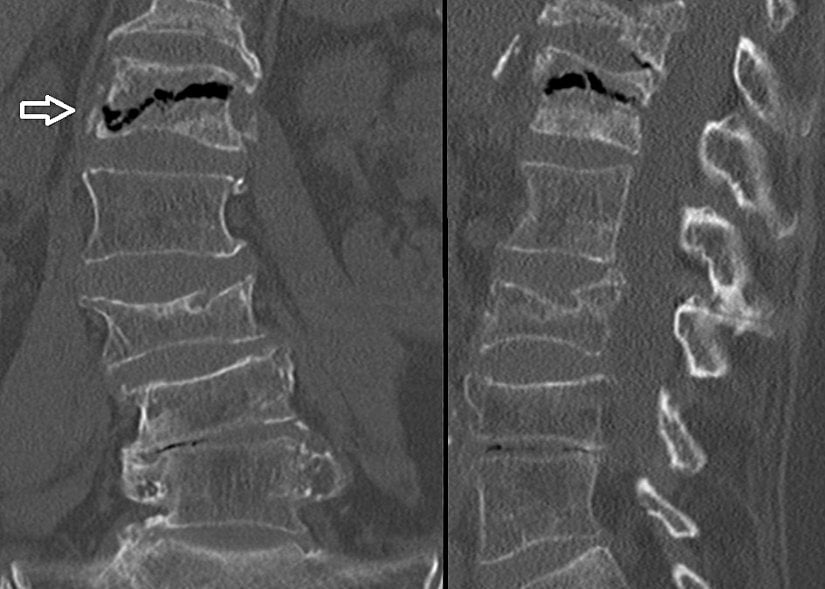

BT taramaları, azaltılmış zayıflamanın merkezi veya çevresel alanlarını gösterir. Yeniden biçimlendirilmiş sagital ve koronal görüntüler subkondral kırıkları ve eklem yüzeyinin çökmesini gösterir. Düz radyografik bulgular normal olduğunda BT bulguları kemik nekrozu ile ilişkili ince trabeküler düzensizlik gösterebilir. Eklem yüzeylerinin çökmesi veya burkulması daha ileri hastalığı gösterir ve tedavi seçimini etkiler.

Konvansiyonel radyografide olduğu gibi, BT kemik enfarktlarının tespitinde duyarlı değildir. Bununla birlikte, BT taramaları, düz radyografilerde olduğundan daha erken kemik enfarktüsünün teşhis edilmesine yardımcı olabilir. BT'nin kemik enfarktüsü tanısında duyarlılığı MRG ve kemik sintigrafisinden daha düşüktür.

Düz radyografide olduğu gibi, bir kemik enfarktüsünün erken BT özellikleri, özellikle uzun kemiklerin metafiz bölgesinde özgünlükten yoksundur. Belirsiz radyolüsensler enfeksiyonları ve neoplastik süreçleri taklit edebilir.

BT taraması diğer tekniklerin tamamlayıcısıdır, ancak radyonüklid görüntüleme veya MRG kadar hassas değildir. Düz radyografik bulgular normal olduğunda BT taramaları kemik nekrozu ile birlikte ince trabeküler düzensizlik gösterebilir. Orak hücre hastalığı olan hastalarda kemik enfarktüsünü osteomiyelitten ayırmada ultrasonografi faydalı olabilir.